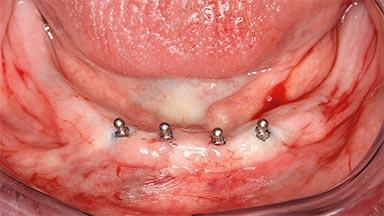

Four Immediately Loaded Mini-Implants Supporting a Mandibular Overdenture

A 74-year-old male patient, a non-smoker, who had been wearing complete dentures for more than 30 years, presented to our clinic complaining about discomfort in connection with his lower denture. The patient suffered from asthma and had a history of cardiac disease and blood pressure disorders. All conditions were medically controlled and stable. The clinical inspection of the oral cavity revealed an ill-fitting complete mandibular denture. The patient expressed the wish for his lower denture to “stop moving when chewing, swallowing, and speaking.” He reported having heard about dental implants and asked whether these could help in “fixing” his lower denture, but also requested non-invasive treatment. The mucosa presented healthy and was free of defects such as pressure sores. An band of keratinized mucosa approximately 2 mm wide was visible. The patient’s mucosal biotype was medium thick to thin.

# of Implants 4

Defining Characteristics Fully edentulous lower jaw to be rehabilitated with two or more implants

Modality 3 or 4 interforaminal implants